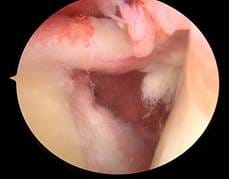

În lipsa obținerii îmbunătățirii dorite la tratamentul conservativ se poate practica tratamentul chirurgical, necesar doar la un procent mic dintre pacienții cu această patologie. Acesta constă în efectuarea unei artroscopii de umăr de către un medic supraspecializat în chirurgia umărului, urmat, de asemenea, de un program individualizat de kinetoterapie. Adresarea către un ortoped supraspecializat în această patologie este importantă pentru alegerea opțiunii terapeutice optime, cu timingul potrivit.